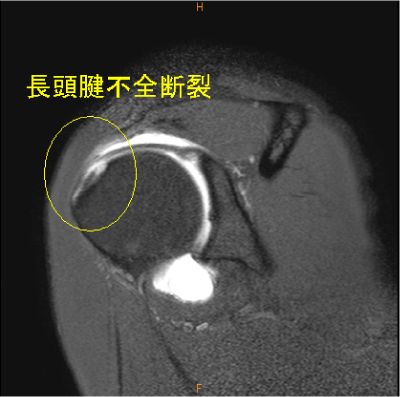

MRI所見

長頭腱の不全断裂は稀な所見である。

MR関節造影で無かったら、描出されて無かった可能性が高い。上方関節唇損傷も認めている。

長頭腱の不完全断裂